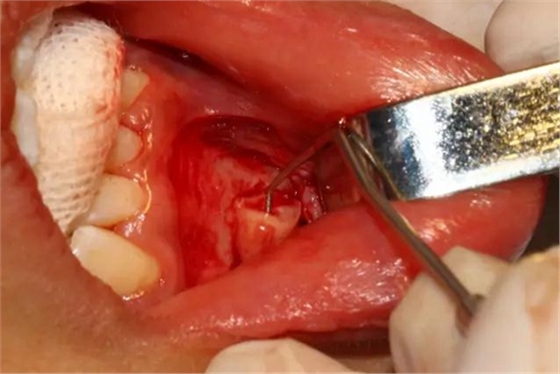

去除含牙囊壁

創(chuàng)口處理

創(chuàng)口內置入膠質銀明膠

關閉創(chuàng)口、對位縫合